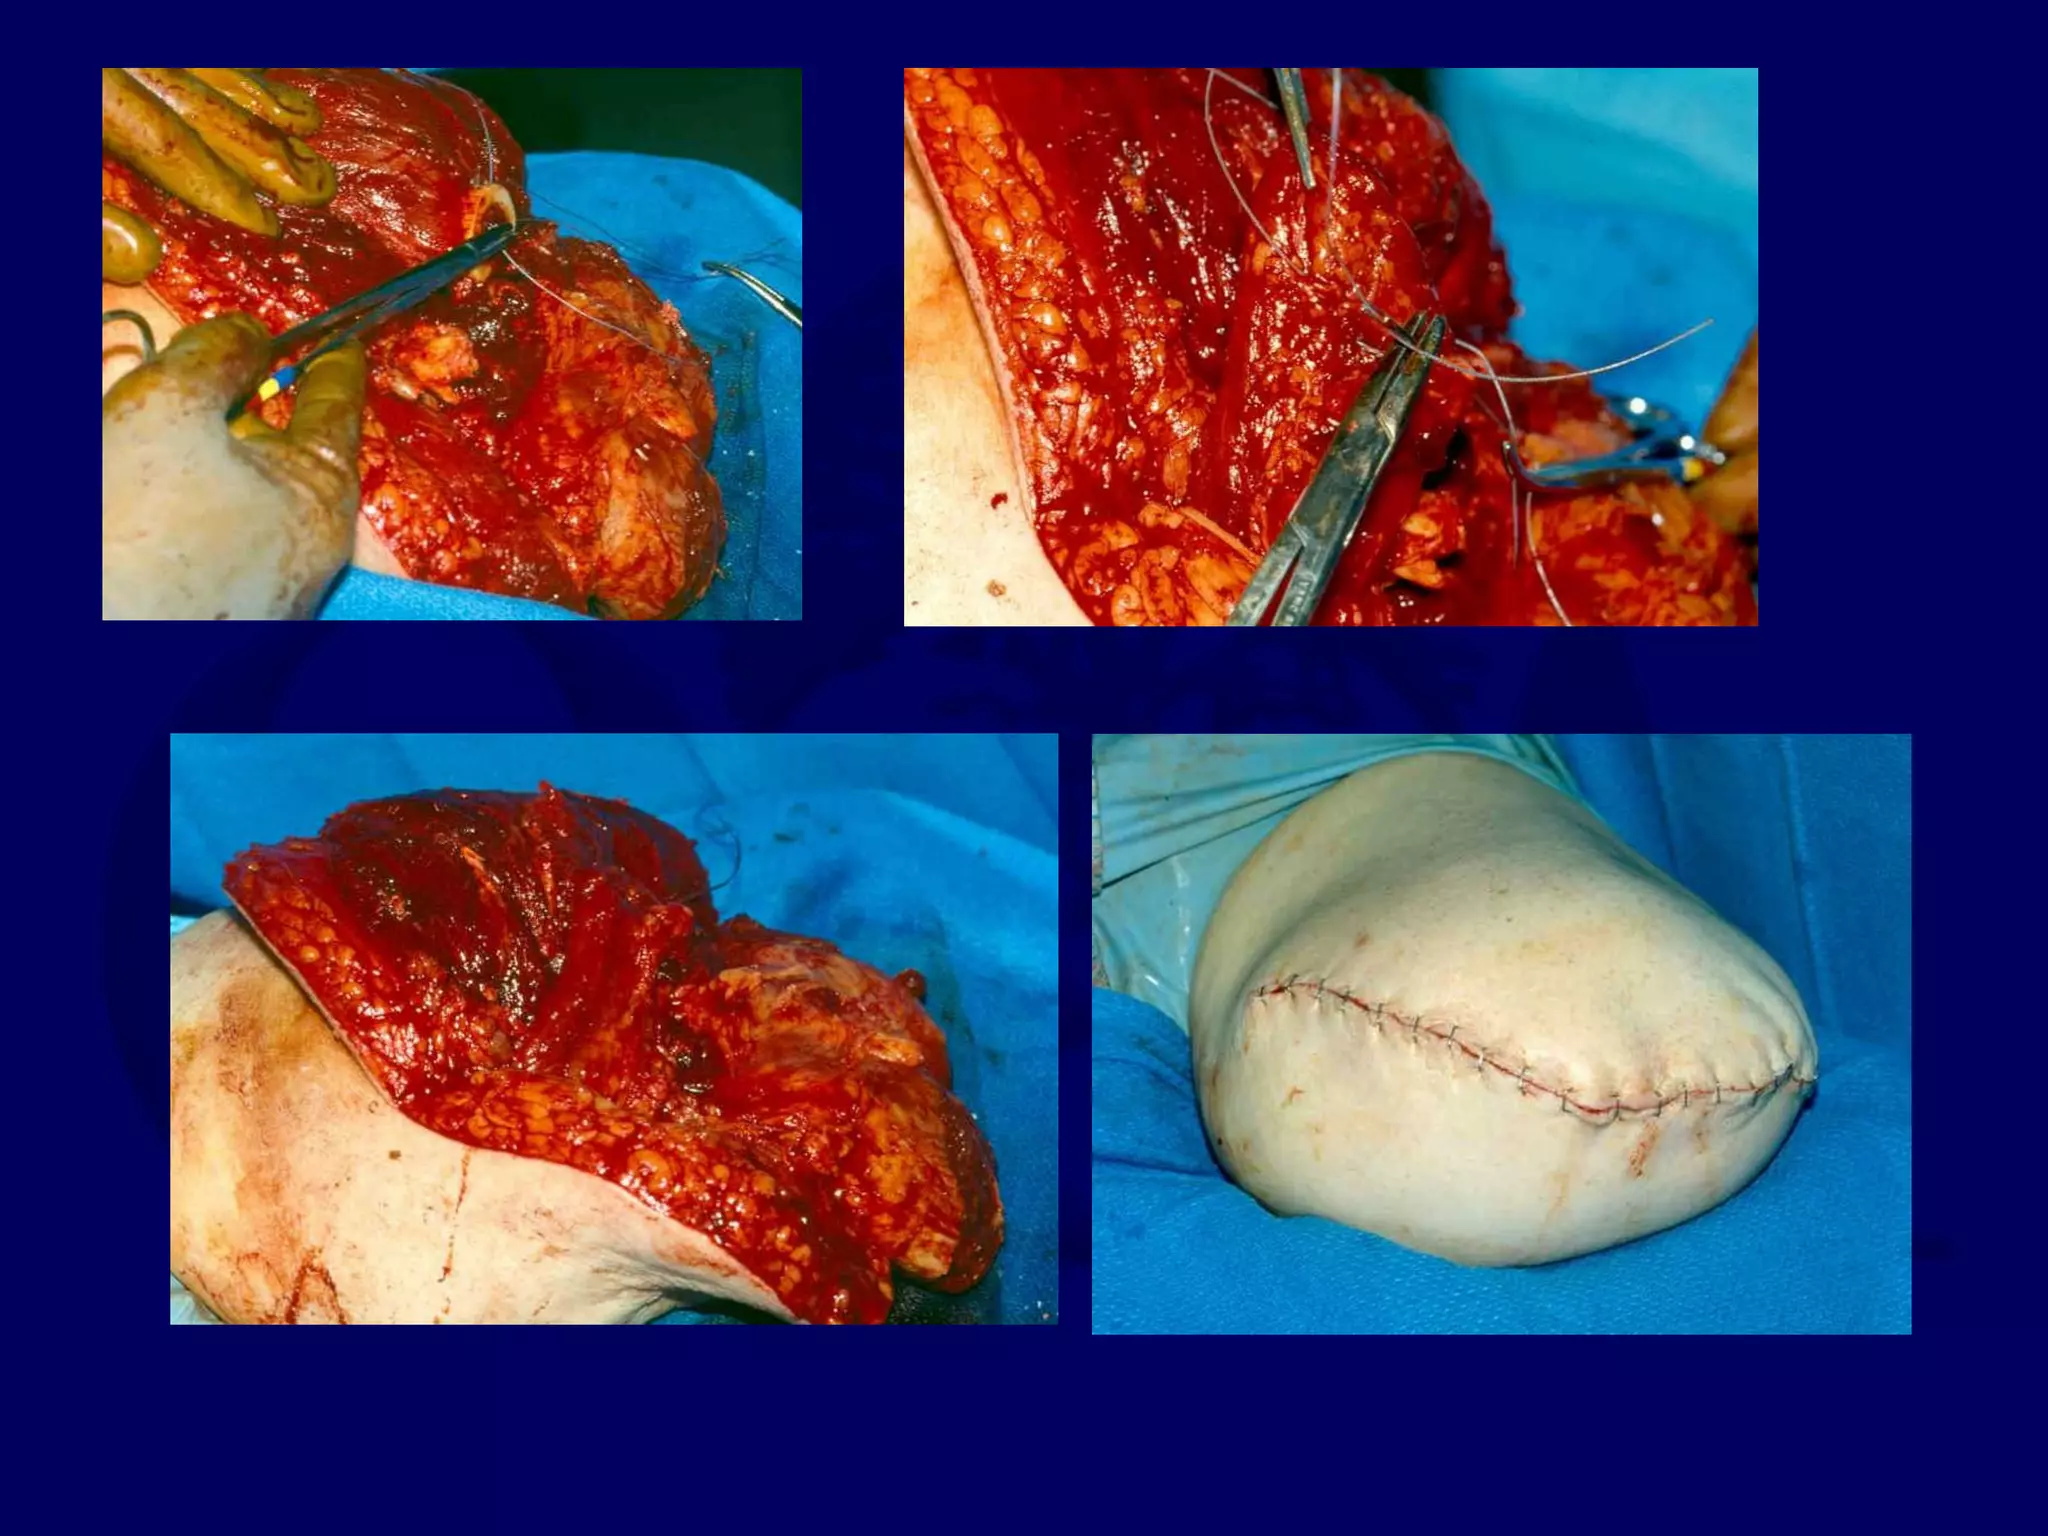

Severe Contusion of the Posterior Flap

Soft Tissue Loss Anterior Aspect

Posterior Flap Failed

41 y.o. Female, Motorcycle Accident

Alaska Sept 2000

Transverse Abdominal Free Flap to Save Knee Joint

41 y.o. Female,

Motorcycle Accident

in Alaska Sept 2000

Why Is This OK?

Good Muscle Coverage that is Not Adherent

Problem is No Sensation, but has good Padding

Proximal Tibial Not Fractured

Healthy Knee Joint

Is It Great - No !

Better Than a Transfemoral - Yes !

25 y.o. Logger - Crush Injury

Severe crush anterior and lateral

Sup Posterior Muscle - Much better than expected!

Soleus brought over the distal tibial

Gastroc split and wrapped medial and lateral

Good Muscle Coverage and Padding, With Healthy Muscle

Skin Graft Applied Over Muscle, Not to Bone

(Even with this, he still gets breakdown over hamstring tendons)

Is It Great - No ! Better Than a Transfemoral - Yes !